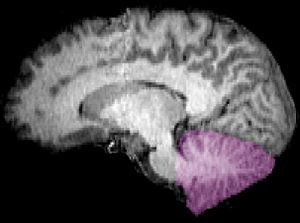

Imagem de ressonância magnética de um cérebro humano. O cerebelo está marcado na cor púrpura. Crédito: wikimedia

O cerebelo (veja sua localização no cérebro na imagem ao lado) é um dos centros de controle motor do cérebro. Nele, milhares de células de Purkinje coletam informações das demais áreas cerebrais e as direcionam aos neurônios motores que ativam os músculos. Cada uma dessas células recebe sinais de uma fibra trepadeira que, por sua vez, coleta dados dos músculos aos quais o sistema está conectado. Segundo Medina, o que mais impressiona nas fibras trepadeiras é o fato de não se tratarem de meros neurônios sensoriais, pois “elas não apenas dizem ‘Algo tocou minha face’; elas dizem ‘Algo tocou minha face quando eu não esperava'”.